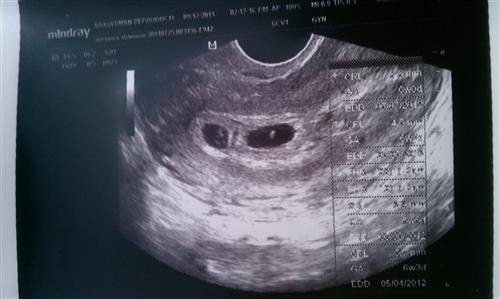

HERE!!!! Our BOTH had heartbeats today!!!!

I'm still amazed.... in awe really. Thank you for helping to put my mind at ease these past 5 days. If all continues to go as planned, I'm sure I'll have tons of questions for you guys! Image Attachment(s):

isnt this just the best picture you've ever seen, i cried the first time i saw a picture

Yup. I've cried twice already and I'm sure I will do it again on Saturday.